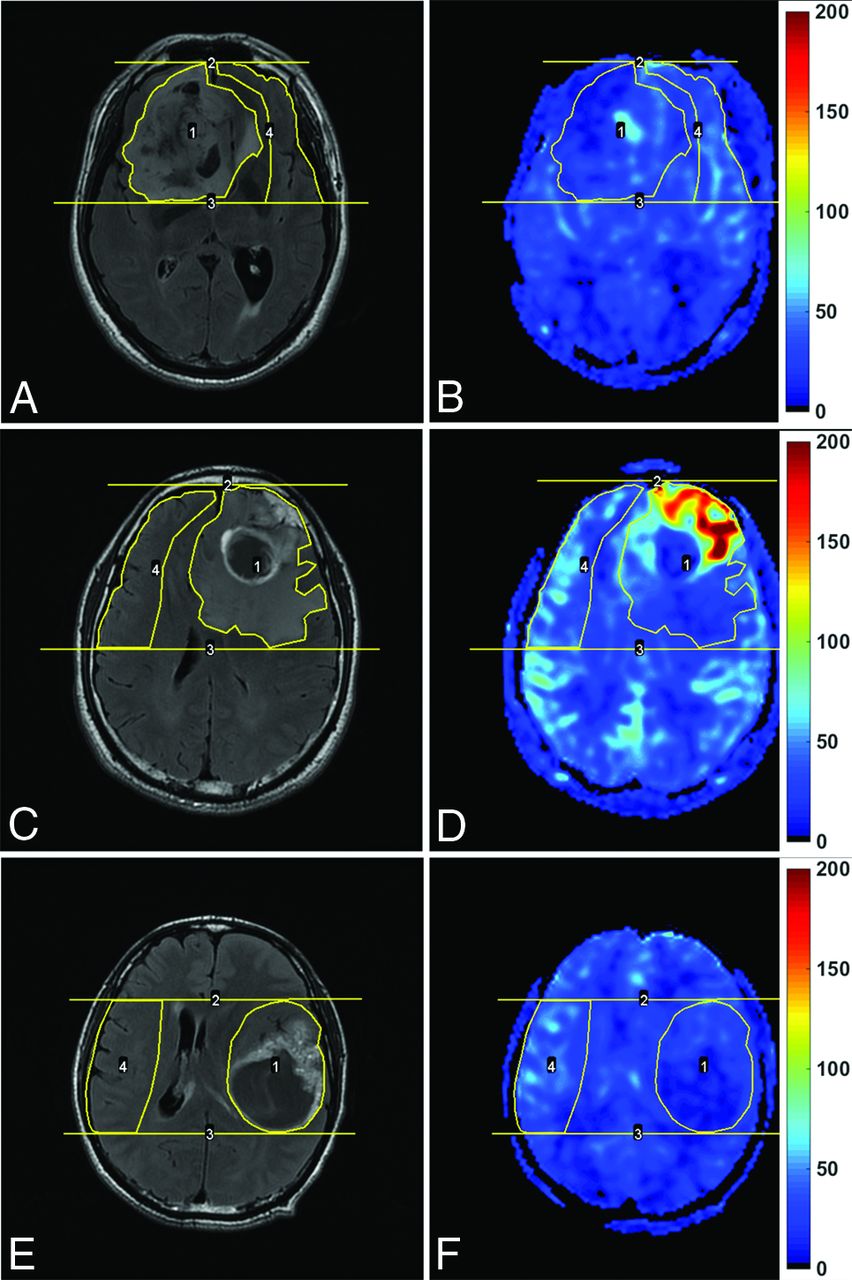

The CBF images were all coregistered to the contrast-enhanced T2-FLAIR images by using SPM12 (www.fil.ion.ucl.ac.uk/spm). The analysis of the images was performed with ImageJ, Version 1.49 (National Institutes of Health, Bethesda, Maryland). The ROIs were manually placed on the contrast-enhanced T2-FLAIR images by 1 expert neuroradiologist with 20 years' experience, who was blinded to the pathology of the tumors. Before ROIs were drawn, the image section that was speculated to contain the tumor area with the highest tumor blood flow was chosen by referring to the CBF maps. Areas with an abnormal signal in the enhanced T2-FLAIR images were all included. Another rectangular ROI was drawn to include contralateral gray matter areas. Then ROIs were copied to the corresponding CBF maps, as shown in Fig 1. The maximum CBF values (CBFmax) in ROIs were obtained. Then the relative CBFmax (rCBFmax) was calculated by dividing the CBFmax in the tumor ROI by the CBFmax in the contralateral ROI.

Enhanced T2-FLAIR images (A, C, and E) and CBF maps (B, D, and F) of a 69-year-old man with oligoastrocytoma (WHO grade II; Ki-67 index, 10%), a 42-year-old man with glioblastoma (WHO grade IV; Ki-67 index, 20%), and a 43-year-old man with glioblastoma (WHO grade IV; Ki-67 index, 60%), respectively. Note that blood flow is significantly elevated in the glioblastoma with a relatively low Ki-67 index, while it is not elevated in the glioblastoma with a very high Ki-67 index. The unit for CBF maps is milliliters/100 g/min.

The manifestations of an LGG, a GBM with a low Ki-67 index, and a GBM with a high Ki-67 index in contrast-enhanced T2-FLAIR images and CBF maps are shown in Fig 1. Our evaluation of the interobserver concordance for parameters showed excellent agreement. The intraclass correlation coefficients for the measurement of tumor CBFmax, contralateral CBFmax, and rCBFmax were as high as 0.995, 0.860, and 0.987, respectively. Furthermore, there was a very strong correlation between CBFmax and rCBFmax (r = 0.941).